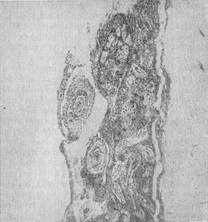

![]() Рис. 8. Хронічний спинальний (переважно продуктивний) туберкульозний лептопахименингит. Різко виражені зміни в оболонках; спаяние корінців, освіта туберкулов, продуктивні васкуліти е різким звуженням просвіту судин оболонок. |

Під впливом специфічного лікування спостерігається значне зменшення або ліквідація типового для початкових фаз хвороби ексудативного компонента, патоморфологічної процес набуває пролиферативно-продуктивний характер (цветн. рис. 2). При пізно почате лікування патологічний процес в оболонках може протікати по типу продуктивного лептоменингита (рис. 8), поширюючись на оболонки спинного мозку, корінці, судини, а також на мозкову тканину (цветн. рис. 3).